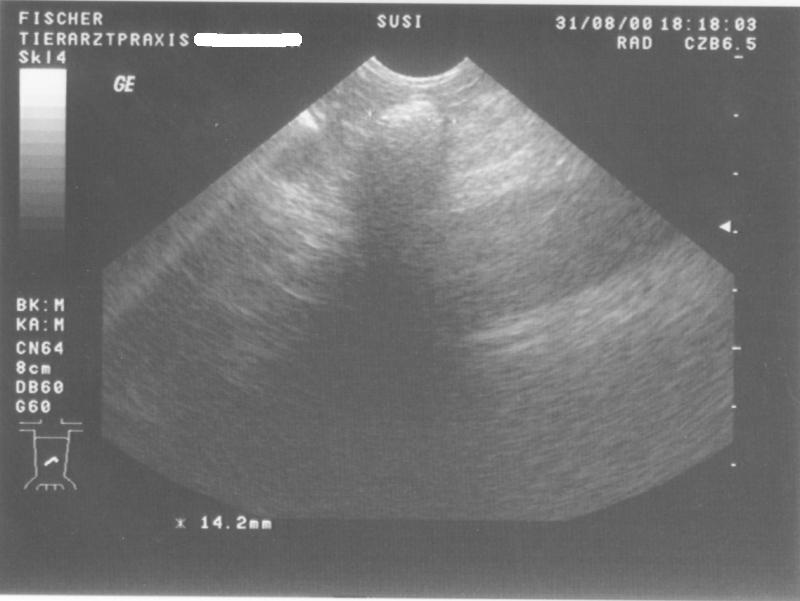

Ultarschall1 Ultarschall2 zurueck